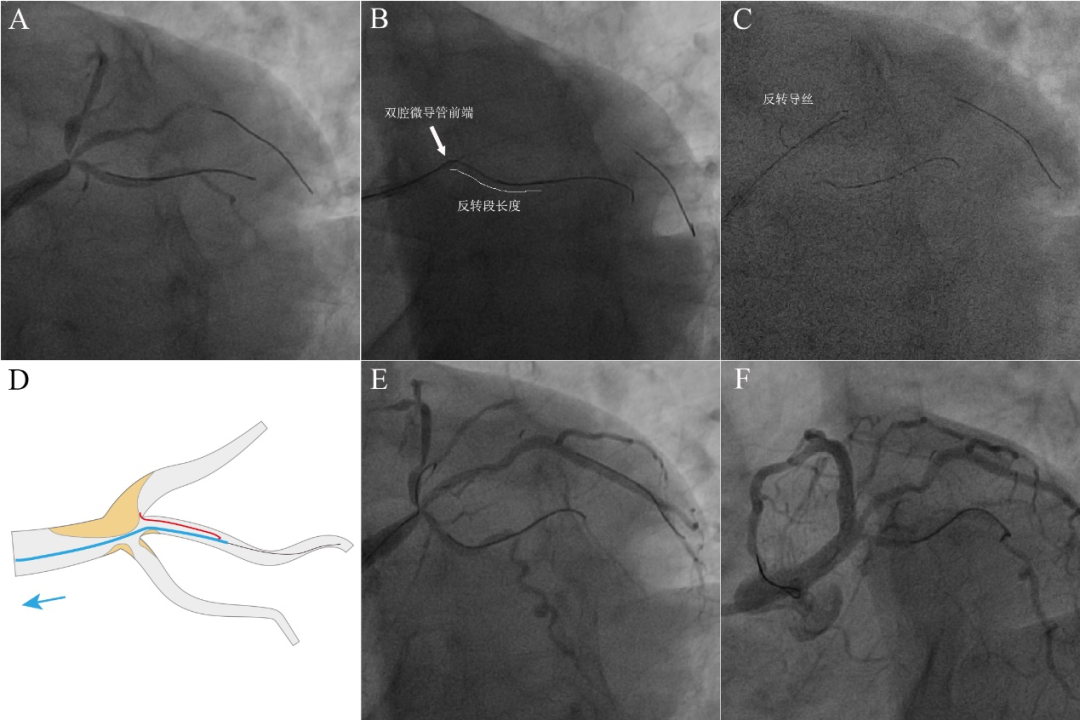

图5 体内反转导丝技术辅助左主干四分叉病变PCI。56岁吸烟男性,反复活动后胸闷1月。冠脉造影示前四叉病变,前降支开口狭窄95%。7F EBU 3.5指引导管到位,Fielder XTR导丝反复尝试无法进入前降支开口。沿中间支Sion导丝送入Crusade双腔微导管,沿双腔微导管OTW腔送入Fielder XTR,反复尝试也未能送入前降支开口(A)。仔细观察前降支开口疑似极度成角,尝试体内反转导丝技术。直接将双腔微导管OTW腔的XTR导丝(反转导丝)送入回旋支约30mm,然后将双腔微导管中心腔出口送至中间支开口处(B),将“反转导丝+双腔微导管”作为一个整体同时前送,XTR导丝体内形成反转袢,直至反转导丝脱离回旋支。其后操作同经典反转法:逐渐回撤“反转导丝+双腔微导管”(C-D),并微调反转导丝方向进入前降支(E)。最终前降支-左主干植入支架,结果良好(F)。